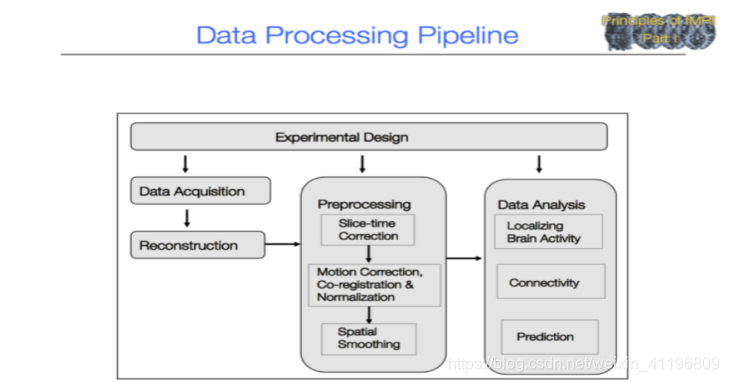

fMRI数据的处理过程

⁃ 数据获重建过程

⁃ 预处理过程:时间校准,头动校准,配准与标准化,空间平滑处理

⁃ 数据分析过程:定位大脑活动、连接强度分析、预测

图1为fMRI数据预处理流程